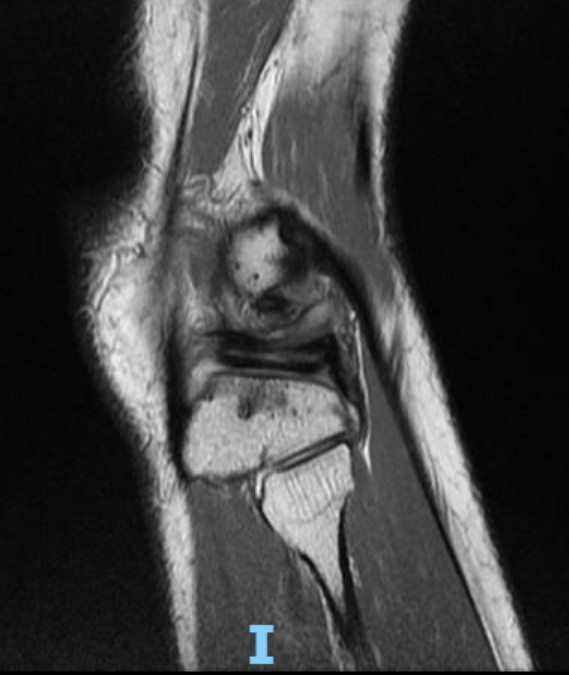

An MRI scan of his right knee was done to confirm the diagnosis.

The clinical diagnosis was a lateral meniscus horizontal cleavage tear with a large lateral meniscal cyst.